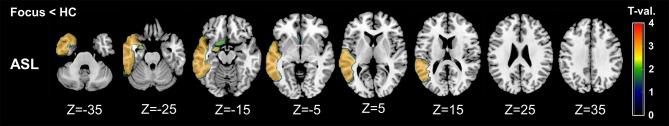

Despite the increasing use of arterial spin labeling (ASL) in patients with epilepsy, little is known about its brain regional distribution pattern, including diaschisis, and its correspondence with FDG-PET. Here, we investigated the regional match and mismatch between FDG-PET and ASL in temporal lobe epilepsy (TLE). We recruited 27 patients with unilateral TLE, who underwent inter-ictal ASL and FDG-PET scans. These images were spatially normalized using Statistical Parametric Mapping 12, and the regional values in both ASL and FDG-PET were calculated using PMOD software within 20 volumes of interest (VOIs), including the temporal lobe, adjacent cortices, subcortical structures, and cerebellum. ASL images of 37 healthy controls were also analyzed and compared. Whereas, ASL showed significant side differences, mainly in the temporal and frontal lobes, the significant abnormalities in FDG-PET were more widespread and included the insula and supramarginal gyrus. Ipsilateral thalamic reduction was found in FDG-PET only. The detectability of the focus side compared with the contralateral side was generally higher in FDG-PET. The discriminative values in ASL compared with healthy controls were higher in temporal neocortex and amygdala VOIs. There are similar and differing regional distributions between FDG-PET and ASL in TLE, possibly reflecting regional match and mismatch of cerebral blood flow and metabolism. At this stage, it seems that ASL couldn't present comparable clinical usefulness with FDG-PET. These findings deepen our knowledge of ASL imaging and are potentially useful for its further application.